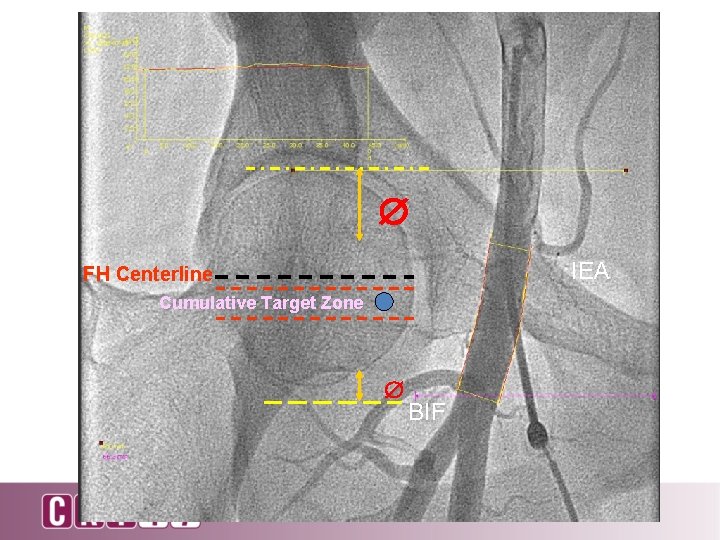

Cumulative Probability of Being Outside Target Zone Above FH Centerline Below

IEA FH Centerline Cumulative Target Zone BIF